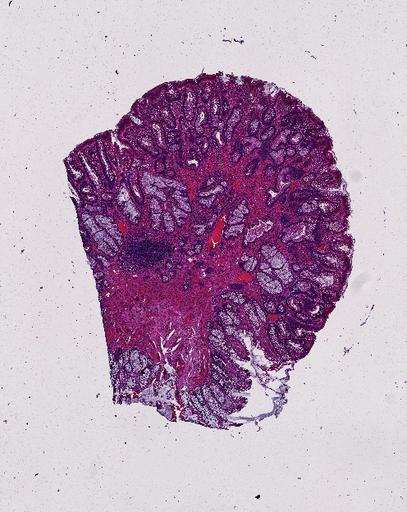

High‑resolution three‑dimensional (3D) tissue atlases promise to redefine how we study cellular architecture‑function relationships in human tissues. Large-scale consortia such as the Human Bimolecular Atlas Program (HuBMAP) systematically build detailed 3D organ maps by profiling serial tissue sections with single-cell spatial technologies. However, an accurate and efficient reconstruction method that can handle atlas-scale datasets remains elusive. We introduce Space-map, an open-source method that integrates single‑cell coordinates with optional histological image features to assemble serial sections into 3D models. Space‑map combines multi‑scale feature matching with large‑deformation diffeomorphic metric mapping, delivering global reconstructions while preserving local micro‑anatomy. To demonstrate the capability of Space-map, we generated a serially sectioned spatial transcriptomics (Xenium, ~2.9M cells) dataset and a spatial proteomics dataset (CODEX, ~2.4M cells). Applying Space-map to these single-cell spatial maps, we built three 3D models for both diseased (colon polyp) and reference colon tissues. These high-resolution 3D models showcase the intricate structure of the human colon across different states. Space-map is fast and highly efficient. We demonstrated its performance and accuracy using in‑house and public datasets. The result shows that Space‑map is 10 times faster and ~2‑fold more accurate than PASTE and STalign, making 3D atlas reconstruction more accessible. Our study provides a new robust and user-friendly software available at https://github.com/a12910/spacemap that can be easily applied for constructing molecular 3D tissue maps of human organs at single-cell resolution.